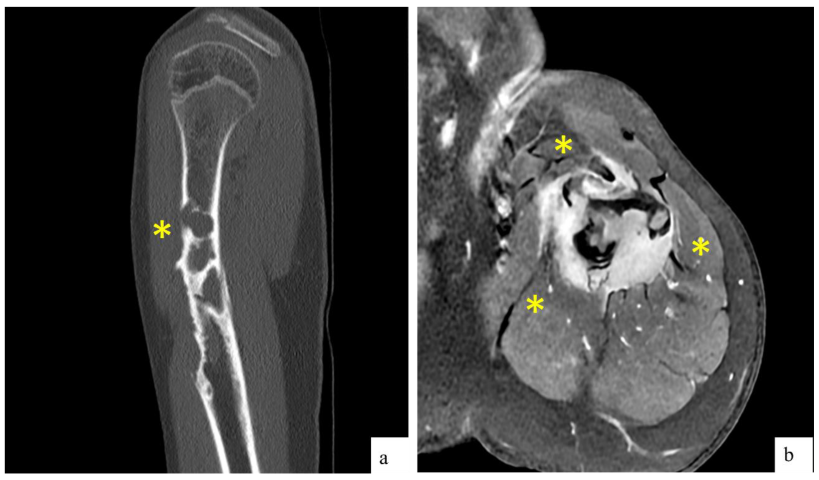

2.1. Clinical and Radiological Findings